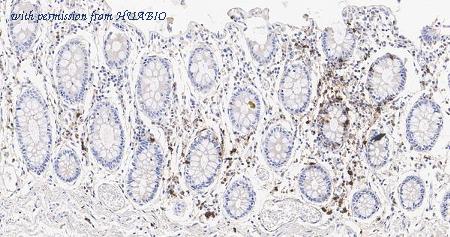

Immunohistochemical analysis of paraffin-embedded human colon tissue with Mouse anti-Myeloperoxidase antibody (EM1901-21) at 1/10,000 dilution. The section was pre-treated using heat mediated antigen retrieval with Tris-EDTA buffer (pH 9.0) for 20 minutes. The tissues were blocked in 1% BSA for 20 minutes at room temperature, washed with ddH2O and PBS, and then probed with the primary antibody (EM1901-21) at 1/10,000 dilution for 1 hour at room temperature. The detection was performed using an HRP conjugated compact polymer system. DAB was used as the chromogen. Tissues were counterstained with hematoxylin and mounted with DPX.